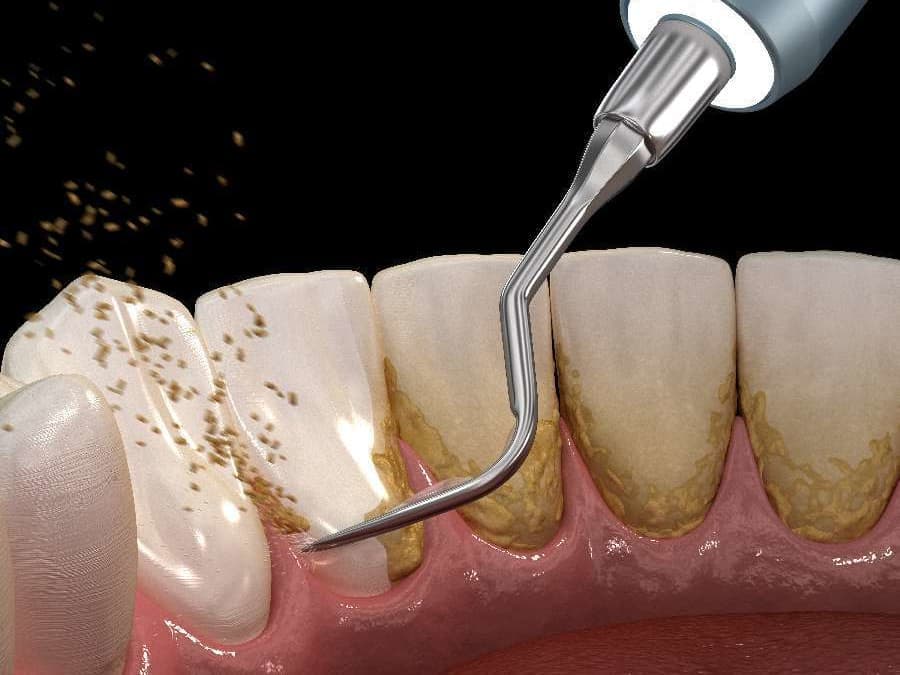

超音波スケーラー

超音波スケーラーは、主に歯肉縁上歯石のスケーリングを行なう際に使用します。

毎秒約25000~40000回の振動によって歯石を破壊し除去します。

また、歯石の除去以外にもクラウンなどの補綴物の除去や根管洗浄にも使用されることがあります。